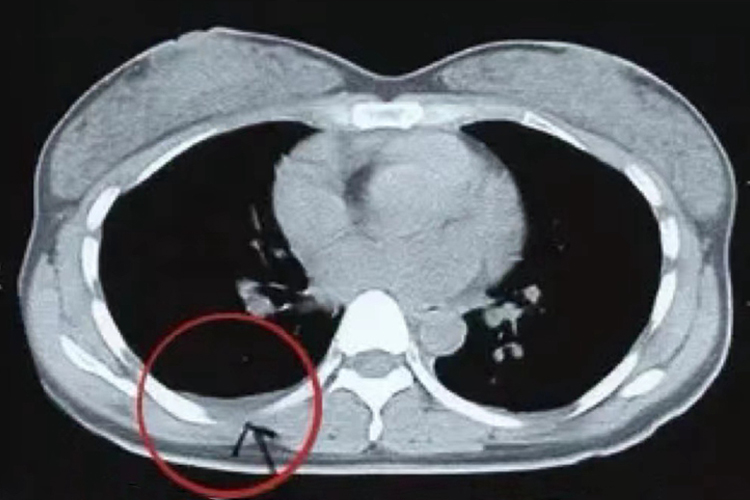

肋骨骨折以第3-10肋较为多见,且多见于腋部及背部,可为完全骨折,也可为不完全骨折。新手看肋骨骨折CT片,能够在肋骨处较直观的看到肋骨连续性中断。

肋骨骨折比较常见,可单发,亦可多发。临床症状与肋骨骨折的数量、部位及是否位移有关。主要症状是胸痛,呼吸及活动时加重,且持续时间较长。多根肋骨多处骨折时,可引起胸壁呼吸反常运动。胸片或常规CT对不全性骨折及无位移的骨折易漏诊,应逐根仔细观察,必要时行薄层CT肋骨三维重组技术进行观察。